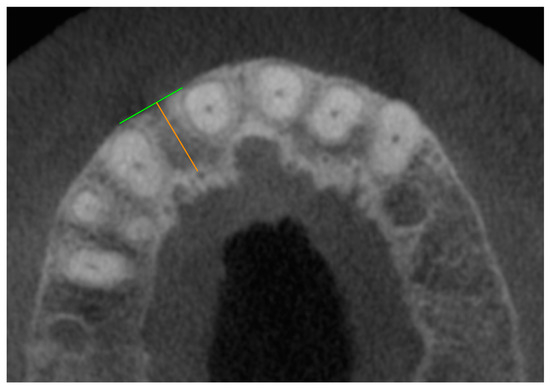

For the measurements, all foramina between the first premolars (teeth 14–24) were taken into account in the axial plane. The foramen to be measured was coded in the axial plane using an assigned number (Figure 1).

Figure 1. Overview of the coding of the foramen position using numbers 1–15 listed in the bottom line of the diagram. Position 1 corresponds to the mediopalatal position at tooth 14, and position 15 corresponds to the mediopalatal position at tooth 24. The even numbers represent the approximal position between two teeth in each case.